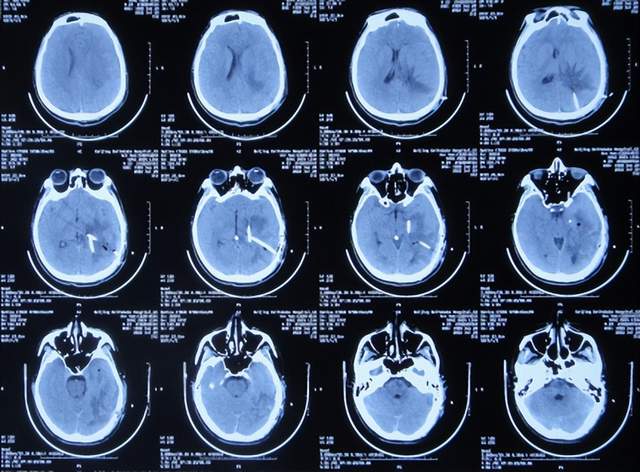

入院后5天即2021年1月18日,查头颅CT增强示颅内占位(图-4)。

图-4:2021年1月18日头颅CT增强